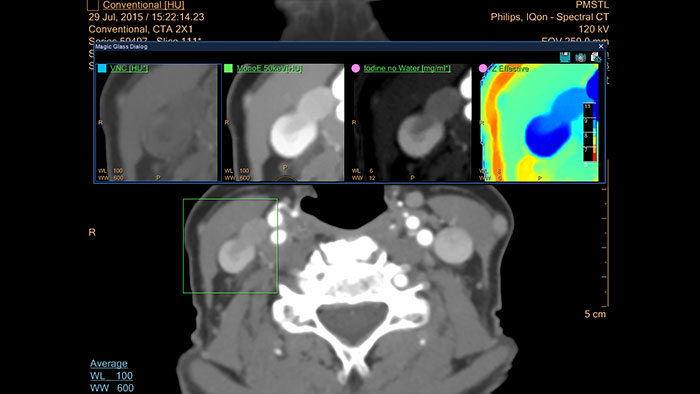

IQon Spectral CT Functionality

IQon Spectral CT is the only scanner to offer CT Spectral Light Magic Glass and CT Spectral Magic Glass on PACS, helping radiologists review and analyze multiple layers of spectral data at once, including on their PACS.

* Standard with the CT Spectral option on IntelliSpace Portal.

IQon Spectral CT* Functionality

The spectral viewer is optimized for analysis of spectral data sets from the IQon Spectral CT Scanner. Obtain a comprehensive overview of each patient quickly and easily, quantify quickly, and assist in diagnosis. It is designed to accommodate general spectral viewing needs with additional tools to assist in CT images analysis.

Benefits

* IQon CT reconstruction provides a single DICOM entity containing sufficient information for retrospective analysis - Spectral Base Image (SBI). SBI contains all the spectrum of spectral results with no need for additional reconstruction or post-processing. Spectral applications are creating different spectral results from SBI.